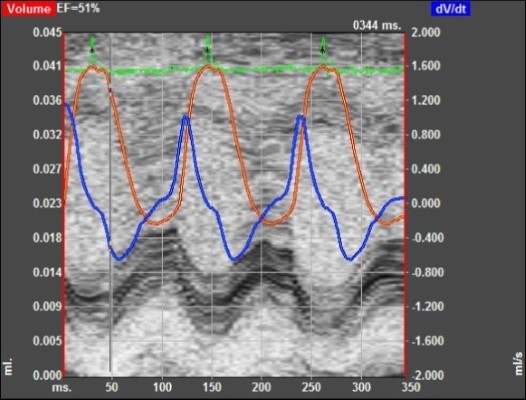

Chronic Ischemia (MI)

4-7 Days Post MI Average 30% Infarct Area. Model Developing Athero